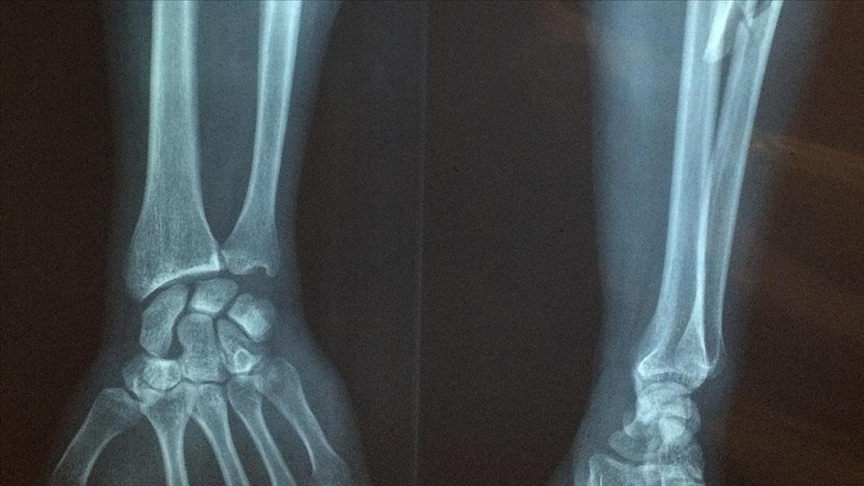

Lapçın, röntgende görülmeyen stres kırığının tespiti için farklı bir görüntüleme yapılması gerektiğine dikkati çekerek, "Bu da MR oluyor. Çünkü MR, kemiğin içerisindeki sıvı düzeyini, ödemi çok rahatlıkla gösterdiği için röntgenin yakalayamayacağı bu süreci çok rahatlıkla yakalıyoruz." bilgisini verdi.